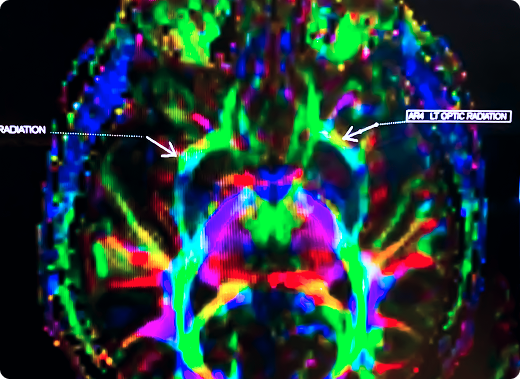

Una imagen colorida del cerebro de un paciente obtenida mediante una exploración de medicina nuclear